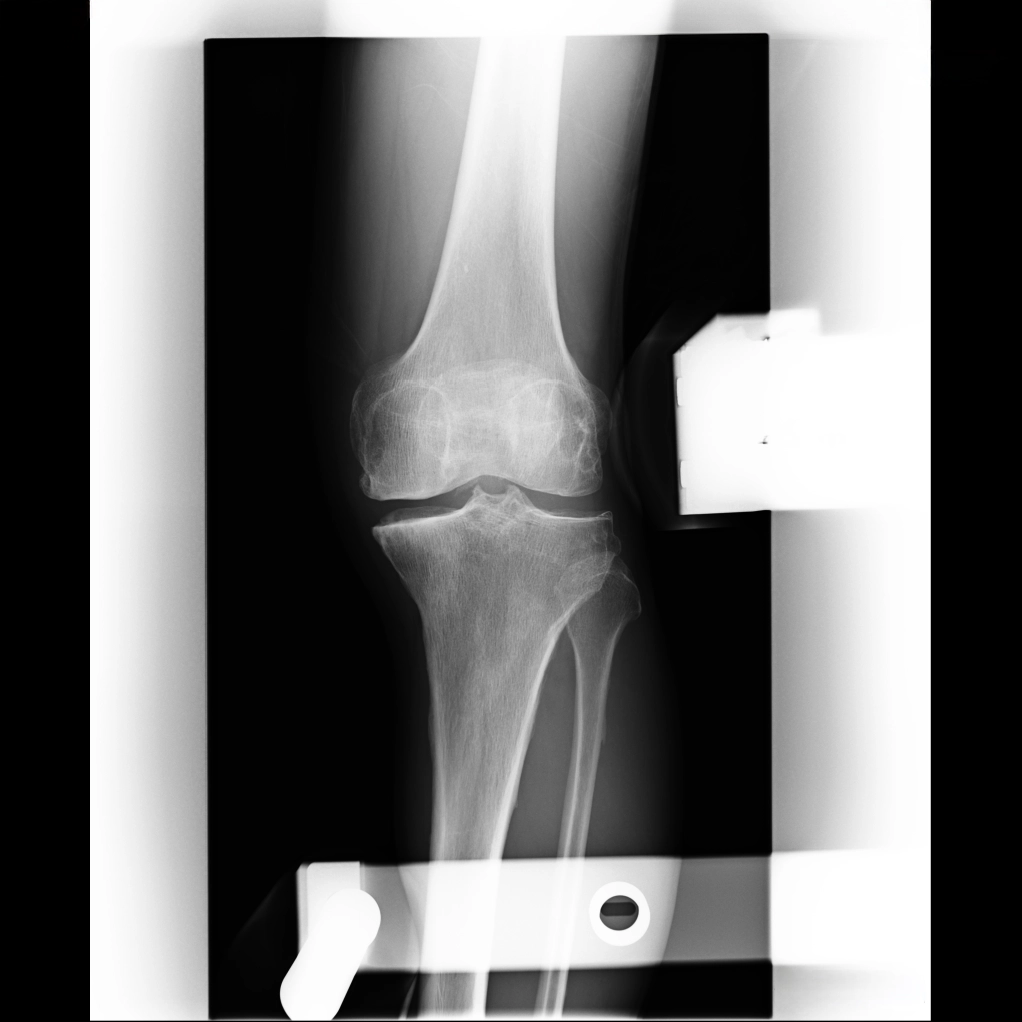

内反ストレス撮影

外反ストレス撮影

次に、同じ患者さんのストレス撮影を見てみましょう。左の内反の写真では、体重がかかることでひざが外側へ押し出され、内側の骨同士がぶつかっています。右の外反の写真は、ひざを外側から内側に押しながら撮影したものですが、内側の関節裂隙(大腿骨と脛骨の間の隙間)が開いているのがわかります。

つまり、この外反歩きを身につけることで、足を振って作られた軟骨が潰れにくくなり、痛みを抑えて歩けるようになるのです。正常な脛骨を切って、2年後に抜釘術を受けなくても、自分の力でその成果を手にできる可能性があるということです。